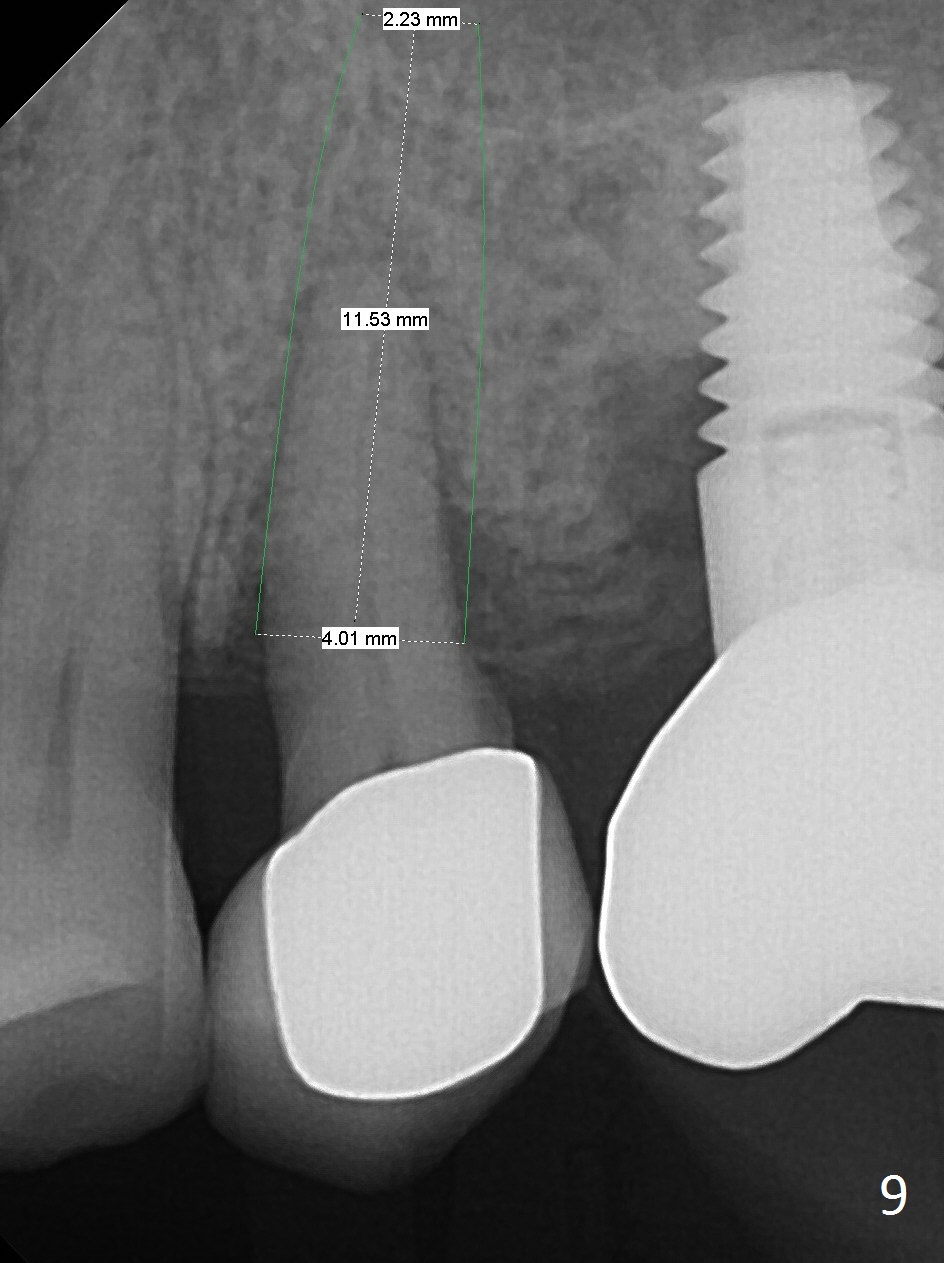

To compensate for bruxism, the implant at #13 should be as large and long as possible. After extraction (Metronidazole), take PVS impression of the socket. Start osteotomy in the distal wall of the socket (Fig.7 red). The initial depth is 11 mm (gingival level). Increase the depth once the trajectory is confirmed (Fig.9). After implant placement (Fig.8 green), place bone graft (red circles) in the mesial portion of the socket as well as in the coronal portion of the implant at #14 (incision). Use a healing abutment (pink), collagen plug (yellow) and suture to close the socket opening.